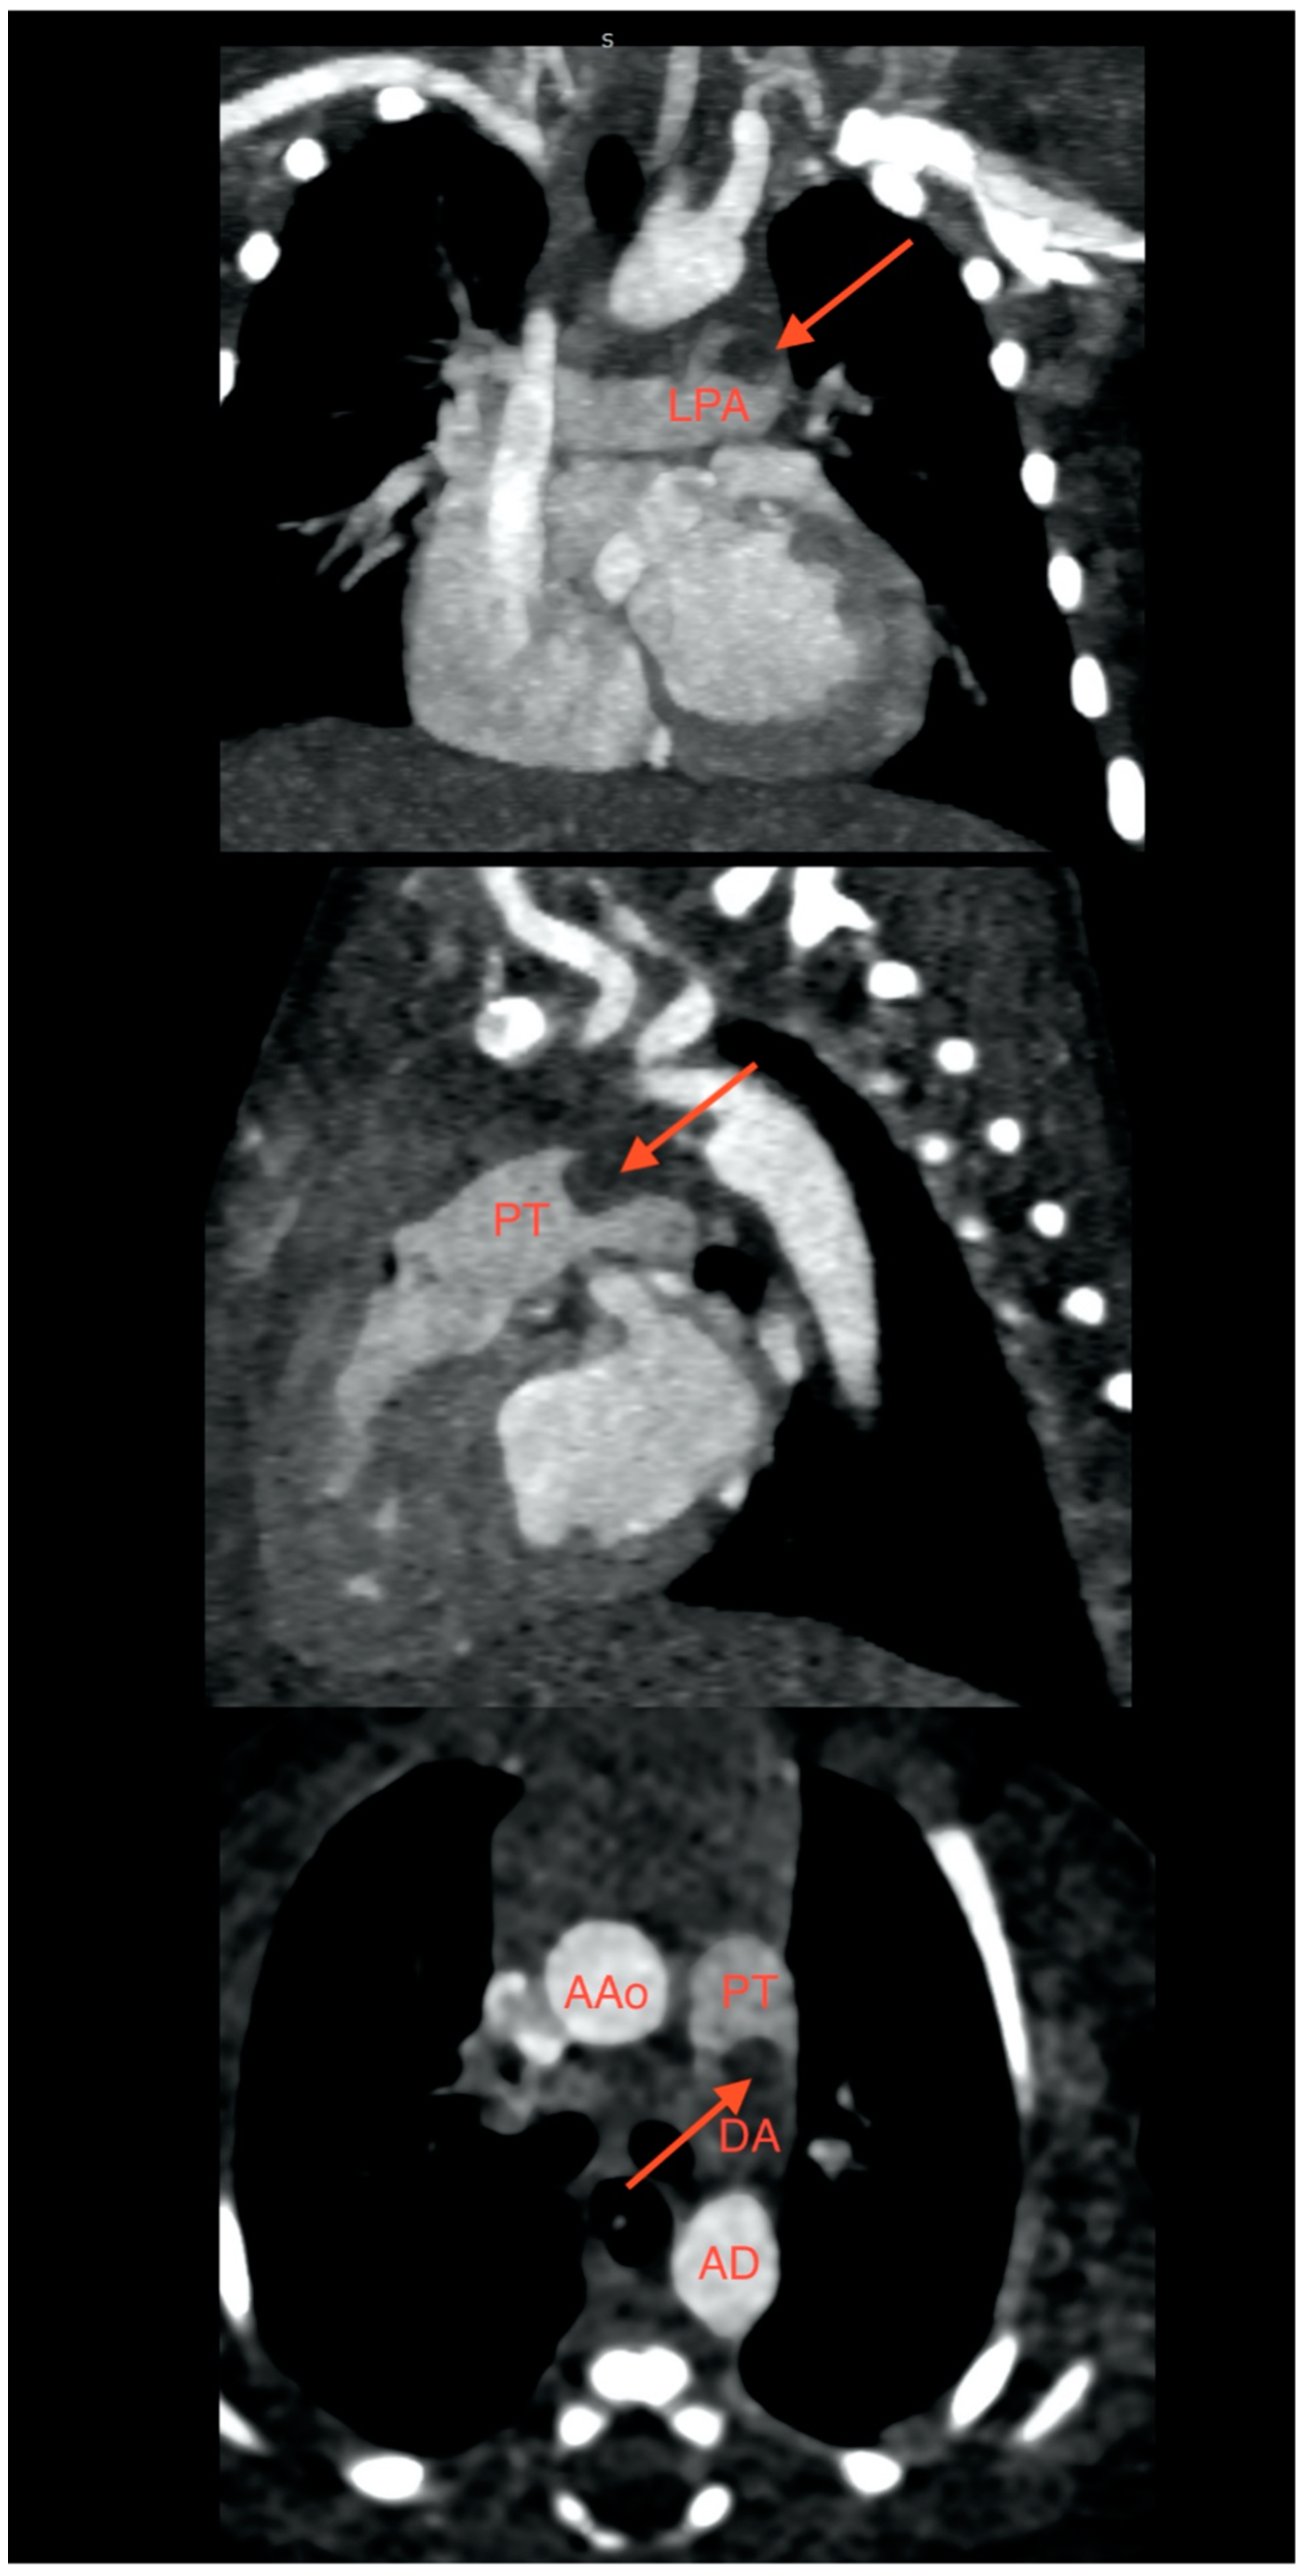

2. Case Presentation